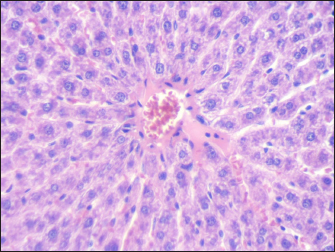

Mouse liver from the control group shows a normal radiant arrangement of the hepatic cells (Fig. 1). Pathological changes in treated liver sections showed an increase in the immune cells’ infiltration, and marked congestion were observed in almost all mice. In group 1, there was hemorrhage, congestion, and degenerated cells (Fig. 2). In group 2, there was congestion of the central vein, infiltration of immune cells, and degeneration of hepatocytes (Fig. 3). Whereas in group 3, the previously mentioned changes were markedly intensified with severe hemorrhage and marked sinusoidal dilatation (Fig. 4). Mouse kidney of control group shows normal cellular appearance (Fig. 5); however, pathological changes in treated kidneys sections reveals congestion, tubular necrosis and cast in some tubule’s lumen, group 1 (Fig. 6). In group 2, there was congestion, tubular necrosis, necrotic debrites in the tubuli lumen and cast (Fig. 7). Whereas in group 3 there was marked congestion, tubular and cellular necrosis, necrotic debrites in the tubular lumen and degenerated cells (Fig. 8).

Fig. 1. Section of mouse liver from control group showing normal radiant arrangement of the hepatic cells (H and E, 400×).